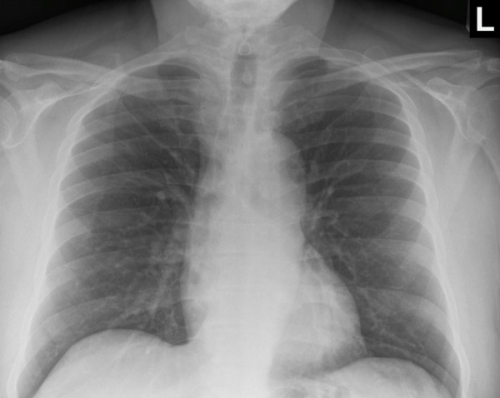

Tool to train medical student's eyes as to what a normal chest x-ray looks like, with over 500 consecutive normal images.